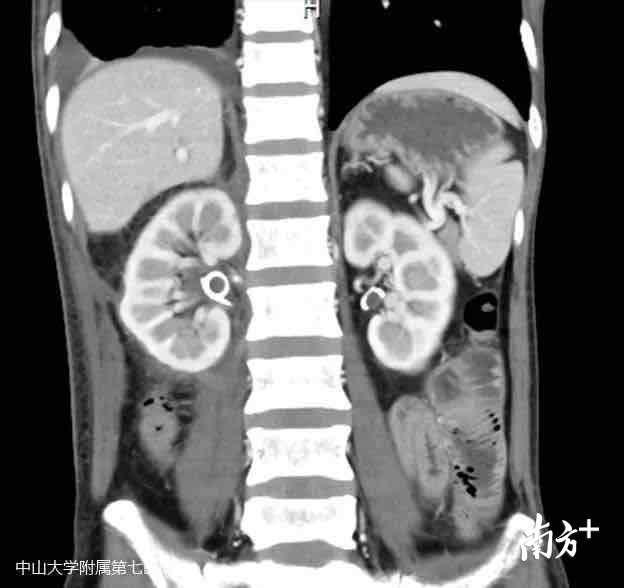

出院复查CT显示,他的右肾也回到正常生理位置,肿物彻底切除干净,康复出院。出院前,林先生向何裕隆教授团队送来了锦旗。